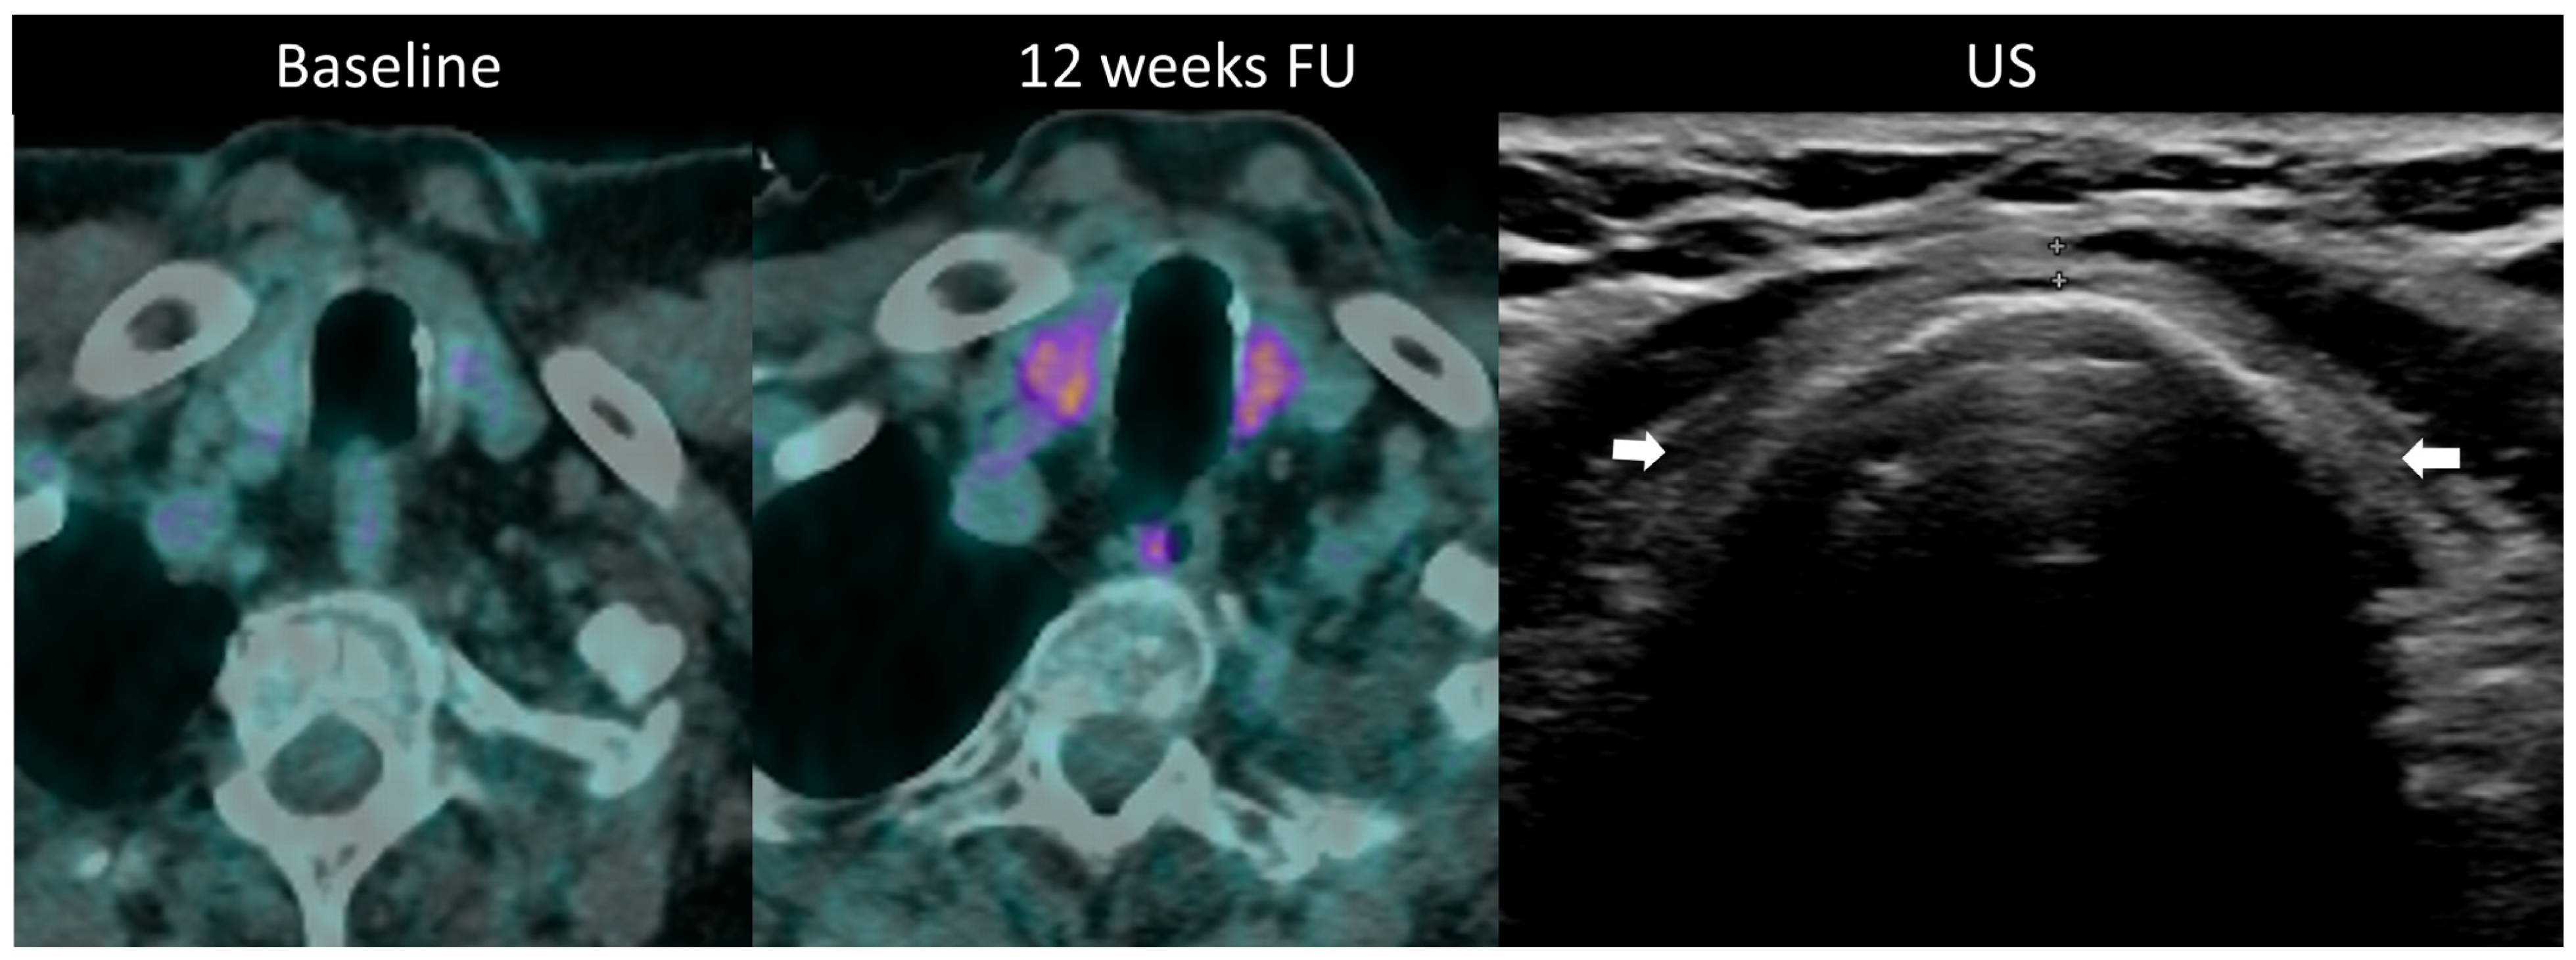

Diagnosis is established through laboratory monitoring of TSH and free T4 every 4–6 weeks [97]. T3 measurement is warranted in hyperthyroidism. Although imaging is not routinely used for diagnosing thyroid disorders during ICI therapy, morphological and metabolic abnormalities are often visible. Ultrasound may be utilized to assess temporal changes such as gland enlargement and heterogeneous echogenicity in the acute phase, as well as the development of hypotrophy in persistent hypothyroidism; hypervascularity on color Doppler imaging is seen in thyrotoxicosis [24]. Diffuse hypoattenuation is often observed on CT scans, accompanied by changes in gland size, and increase in thyrotoxicosis, and a decrease in hypothyroidism [101]. 18F-FDG PET/CT typically reveals increased gland uptake (Figure 10). Importantly, it has been noted that baseline PET/CT demonstrating thyroid hypermetabolic activity is associated with an increased risk of developing ir-thyroiditis.

Figure 10.

Immune-related thyroiditis in a patient receiving chemotherapy and combined anti-PD-1 + anti-CTLA-4 for metastatic lung cancer. At baseline 18F-FDG PET/CT, no thyroid uptake is seen. At week 16, a diffuse moderate metabolic activity of the thyroid gland appeared at PET/CT. The patient developed a grade 2 primary hyperthyroidism. After the resolution of the acute phase, the laboratory tests showed a marked primary hypothyroidism and the ultrasound depicted an atrophic and heterogeneously hypoechogenic thyroid gland (arrows) consistent with a pre-existing chronic thyroiditis.